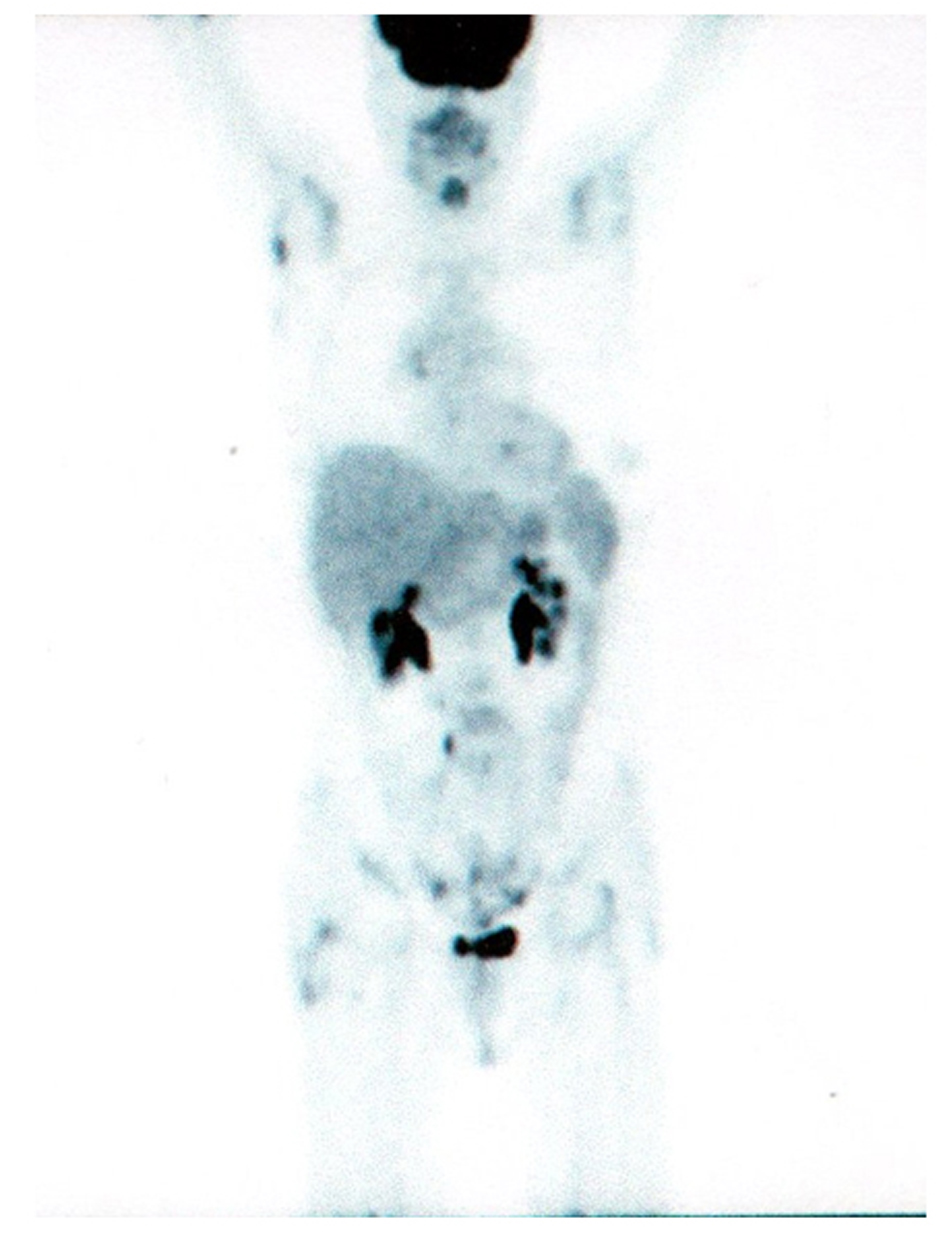

A 64-year-old, non-smoker, female patient was admitted for the first time to our Oncology Department on 1 July 2004. On 15 June 2004, she underwent right colectomy with diagnosis of adenocarcinoma, G3, pT3 N0 MO (Dukes B2, according Astler and Collins). We decided to start an adjuvant chemotherapy with iv folinic acid and 5-fluoruracile for 5 days (Machover schedule); on December 2004, the patient completed 6 cycles of treatment. Following clinical and instrumental controls were negative for disease relapse. On 9 March 2009, a Total-Body CT-scan, during follow-up, showed a nodule (38 × 35 × 29 mm) in the upper lobe of the right lung with lymphnodes on aorto-pulmonary window and Barety. Broncoscopy with aspiration was negative but FDG-PET/CT scan confirmed an uptake in the upper lobe of the right lung (SUVmax: 11.5) with other 3 uptakes: 1 on Barety (SUVmax: 4.4) and 2 on right lung hylum (SUVmax: 4.8). The patient decided to refer temporarly to another hospital. On May, the patient came back to our Institution: on 16 April 2009, she underwent right upper lobectomy and mediastinal adenectomy. The diagnosis was: “poor differentiated adenocarcinoma” (TTF1 +/-; Citocheratine 7 +++; CDX2 -) with metastasis on 11 lymphnodes (pT2 N2 M0 - stage IIIA). Considering the high risk of relapse, we decided to start and adjuvant chemotherapy with carboplatin/gemcitabine for 4 cycles (carboplatin AUC 4 on day 1 and gemcitabine 1000 mg/m2 on day 1 and 8, every three weeks). FDG-PET/CT scan performed on 8 October 2009 was negative. After 7 months, a Total-Body CT-scan showed a slight pleural effusion on right lung without other findings but two neoplastic markers were increased (CEA: 266 ng/ml; CA 19-9: 115 ng/ml). FDG-PET/CT scan performed on 17 June 2010, documented multiple uptakes on bones (ribs, dorsal and lumbar vertebrae, pelvis, left femur, left scapula, sacrum) and an uptake on right hylar adenopaty (Fig. 1). CEA: 311 ng/ml and CA 19-9: 148 ng/ml.

![]() Click for large image | Figure 1. PET/CT scan before gefitinib treatment. |

A search for EGFR-mutation was performed and iv zoledronic acid (4 mg every 4 weeks) was started. An exon 21 point mutation of EGFR has been found and the patient started gefitinib (IRESSA®; AstraZeneca) 250 mg/day on July 2010. FDG- PET/CT scan performed on 11 October 2010 showed the complete remission of all uptakes with reduction of neoplastic markers (Fig. 2). CEA: 21 ng/ml; CA 19-9: 13 ng/ml. The last clinical control was performed on 27 September 2011: the patient was in good condition without symptoms of note. During these 14 months of gefitinib treatment, the patient reported only 1 episode of grade 2 diarrhoea; a skin rash wasn't ever recorded. Total-body CT scan is negative and CEA value is 1.7 ng/ml.